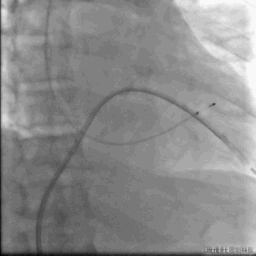

球囊跨二尖瓣

24MM二尖瓣球囊扩张